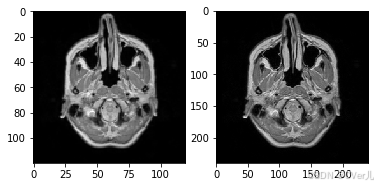

if __name__ == '__main__':

test_dataset = MyDataset(mode='train')

lr,hr = test_dataset[0]

print(np.array(lr).min(),np.array(lr).max())

print(np.array(hr).min(),np.array(hr).max())

plt.subplot(1,2,1)

plt.imshow(lr[0],cmap='gray')

plt.subplot(1,2,2)

plt.imshow(hr[0],cmap='gray')

plt.show()

0.0 1.0 0.0 1.0

<Figure size 432x288 with 2 Axes>